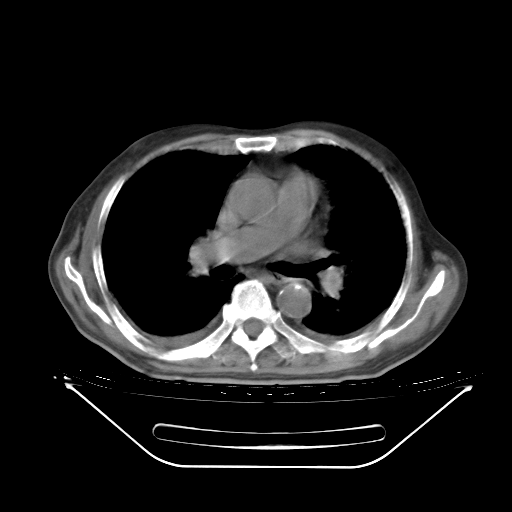

胸腹部CT,诊断意见:左上肺叶钙化灶、左侧胸膜局限性增厚并钙化、胆囊炎。描述部分肺组织呈磨玻璃样改变。